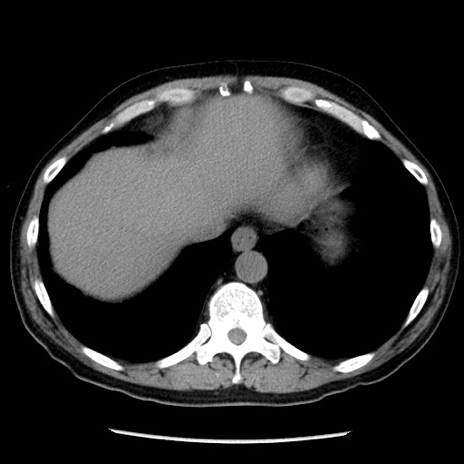

冠状断像

【症例】40歳代男性

【現病歴】2日前から胃痛あり。徐々に周期的な激痛に変化した。本日になっても激痛があるため受診。

【身体所見】意識清明、BT 38-39℃台あり、腹部:膨満、やや硬、右下腹部に圧痛あり。

【データ】WBC 8500、CRP 23.26